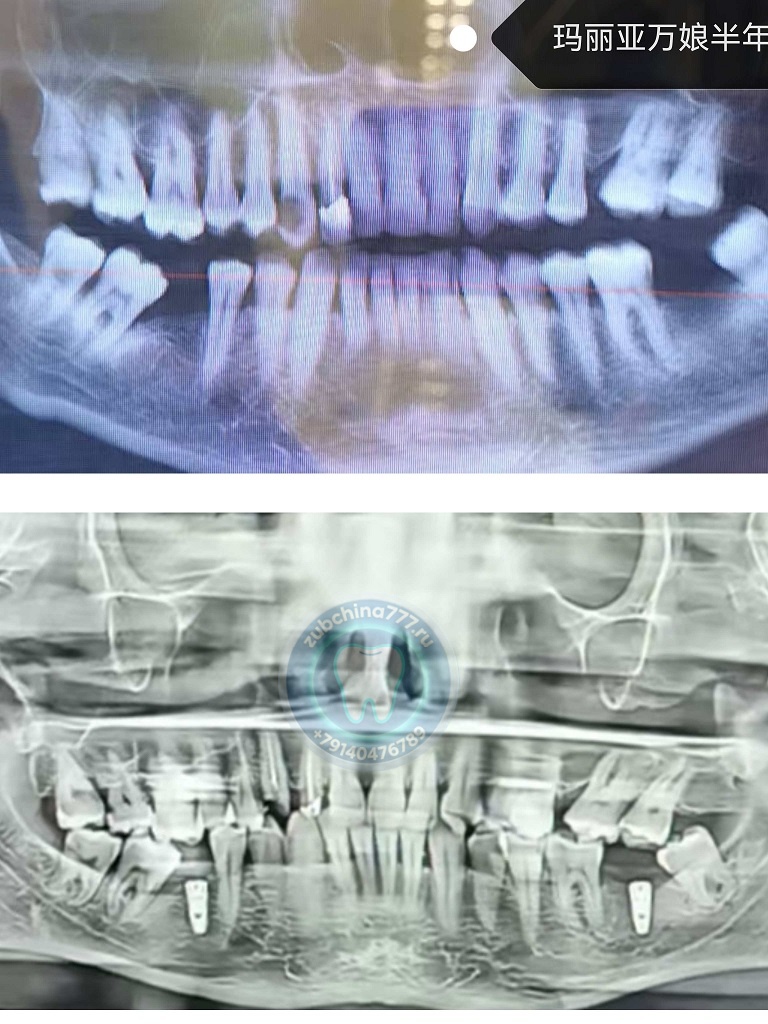

Фотографии пациентов ДО и ПОСЛЕ лечения и протезирования зубов в Хэйхэ

2. Пройдите диагностику в России

Вы можете сделать снимок зубов и провести осмотр в государственной или частной клинике по месту жительства.

3. Отправьте материалы

Пришлите нам рентген-снимки, после чего наши специалисты:

Проведут детальный анализ

Составят план лечения

Определят необходимые процедуры